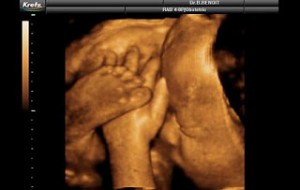

Hamileliğin (Gebeliğin) 35. Haftası Resim ve Video;

Hamileliğin (Gebeliğin) 35. Haftası